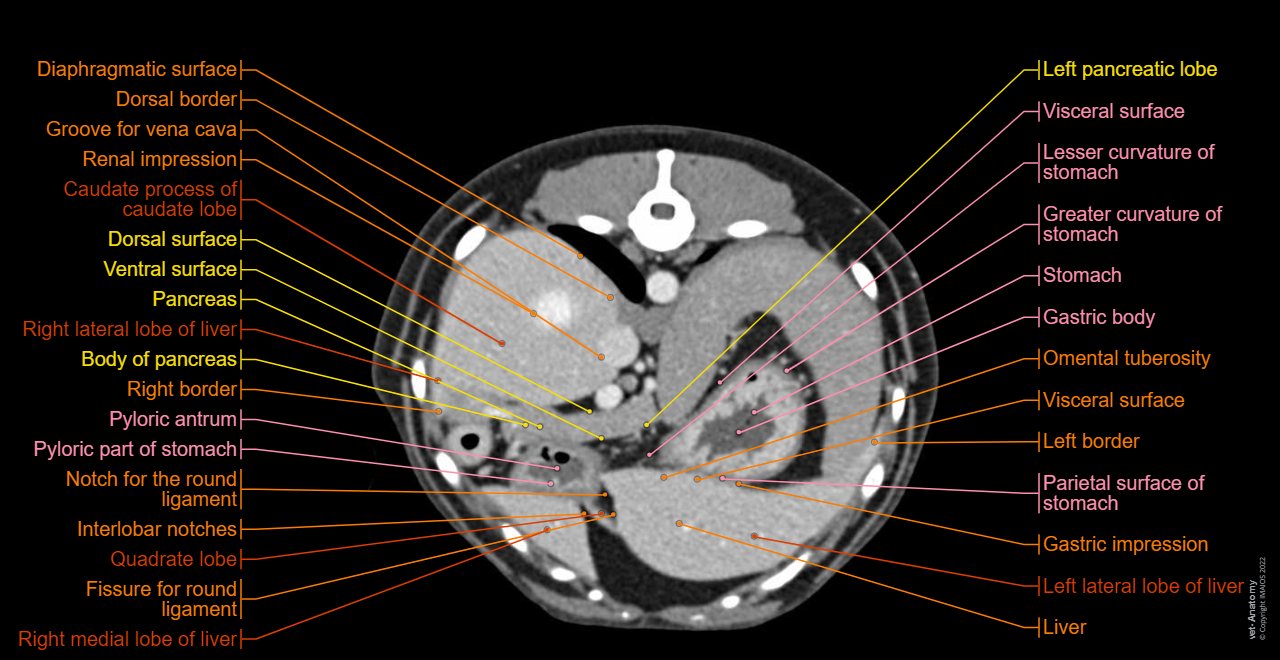

Cross-sectional labeled anatomy of the abdomen and male pelvis of the dog on CT imaging (liver, hepatic segmentation, pancreas, biliary tract, digestive tract, small and large intestine, kidney, bladder, genital organs, peritoneum)

3D - Anatomy atlas - Dog: Liver, Gallbladder, Liver, Pancreas, Spleen